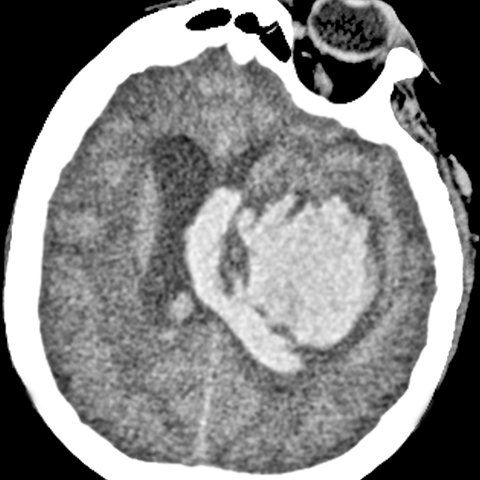

44 year old African American male presented with a sudden onset of a severe headache and slurred speech. [2 of 3]